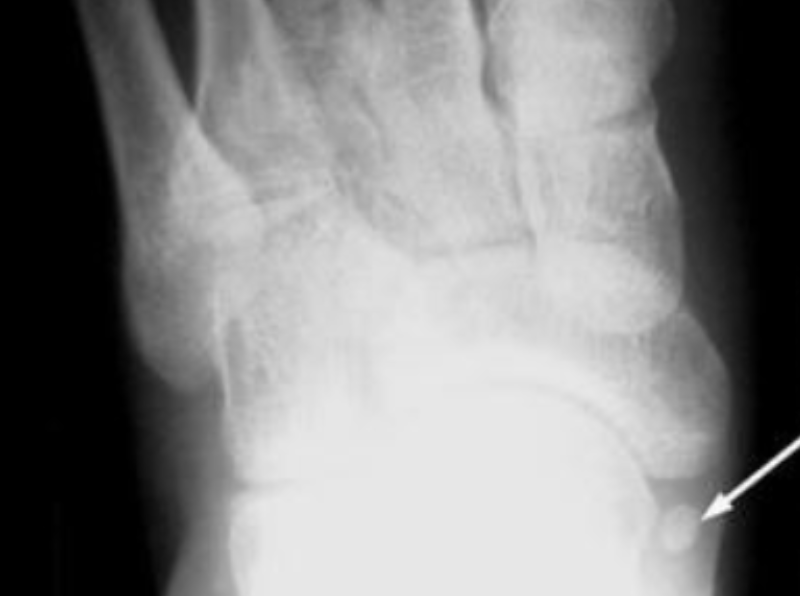

19

Q

Name the accessory bone in the image.

A

Os Intermetatarseum